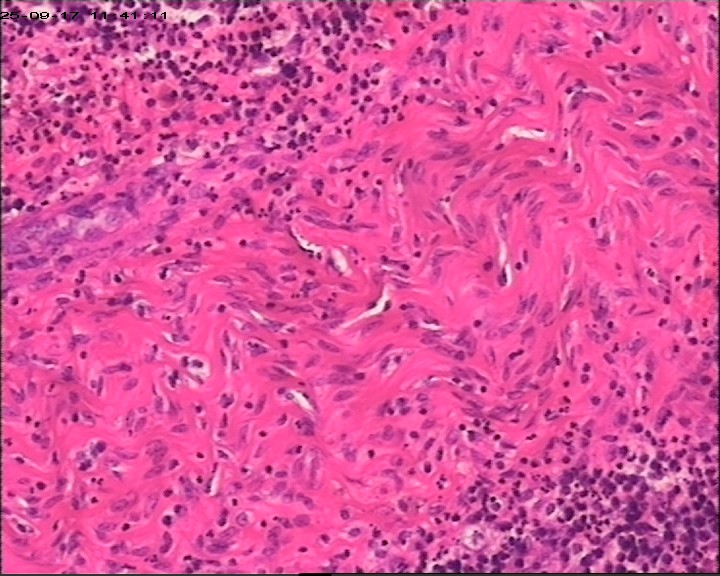

臀部组织,请帮忙看看,谢谢

性别

男

年龄

20岁

临床诊断

一般病史

藏毛窦或囊肿切开术

标本名称

臀部

大体所见

灰白灰黄碎组织一堆,大小为6.5*4*1cm。

描述诊断炎性病变